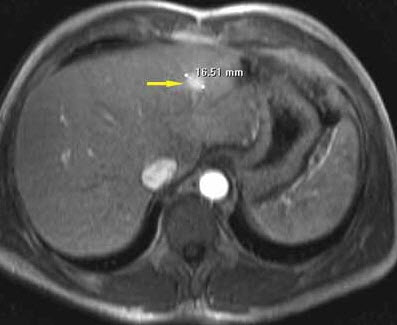

Abdominal MRI is performed to further delineate the hepatic masses. Based on the enhancement pattern during contrast administration, the lesions are characterized as hemangiomas. The largest lesion measures 16.51 mm (Figure 2).